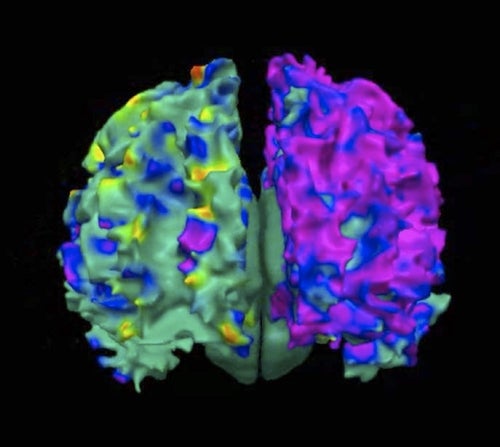

By Francis Koster This is Breast Cancer Awareness Month. Here are some facts about breast cancer you may not know. Sadly, around 40,000 women die ...